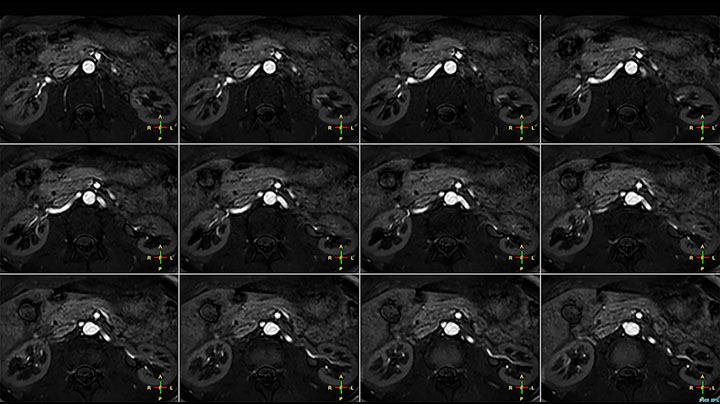

Imaging the renal arteries without contrast agent on Prodiva 1.5T.